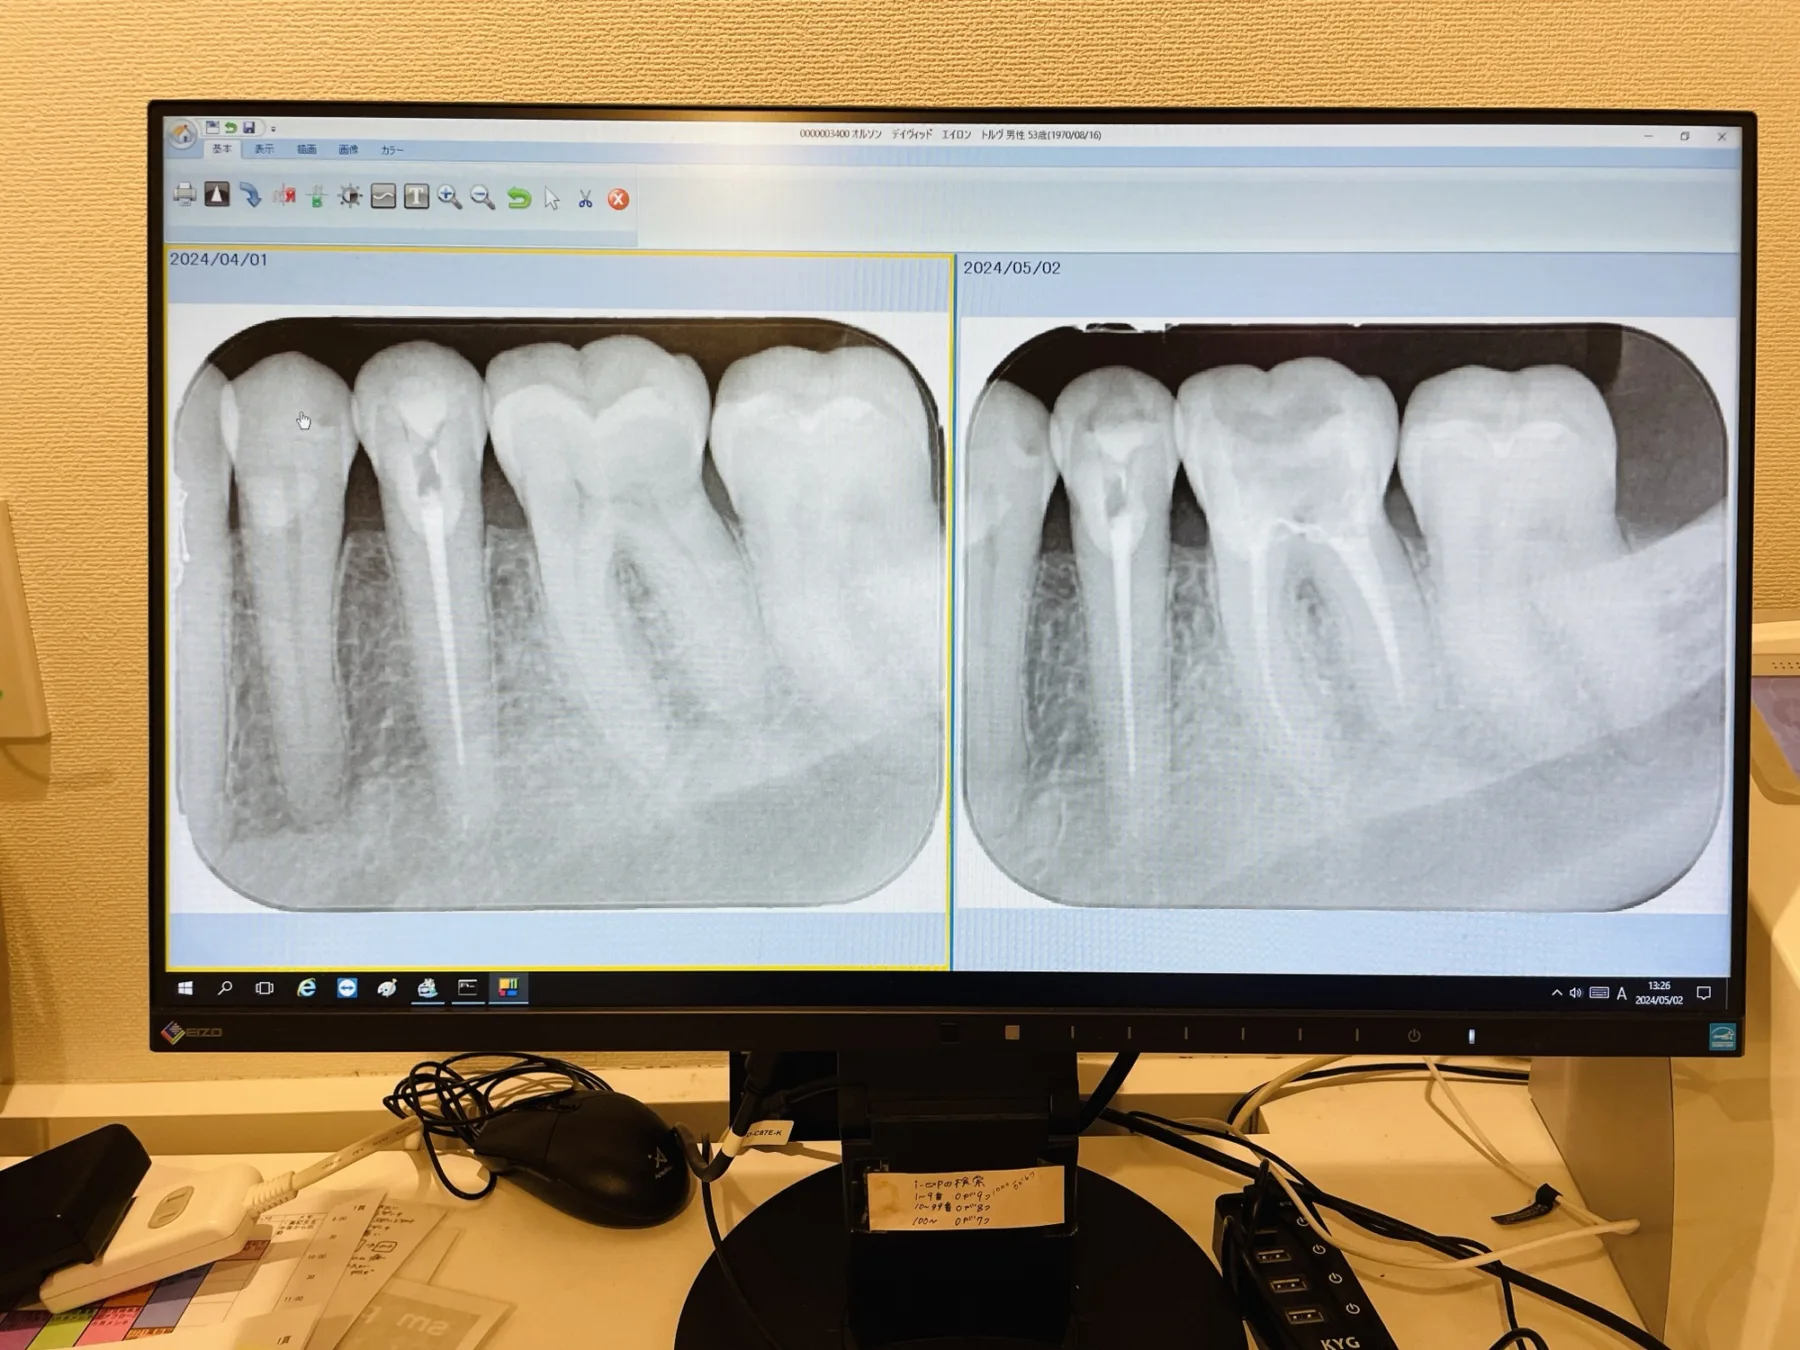

Of late, it seems this is less of a “creative life archive” then a “documentation of survival”… Recently, obviously dental visits adding to the usual hospital appointments to decline a physical, emotional and mental well-being and vigor.

And of course, the obligatory snap of me on the couch looking fantastically excited about going to the dentist, yes again…

A bit confusing but somehow I will survive {Previously went to a fellow closer to the house but it was antiquated equipment, grumpy staff and non-diligent dentist. We’ll see how survive the transportation…}

My initial planned bus route was missed due to “several coffees” this morning… I’m on Plan B and I am 93% sure I am on the correct bus… It still gives me a bit of a walk to the dentist // think I’m gonna have to change dentists – this place is great but transportation is rough.

Now: Slightly more pretty when I smile